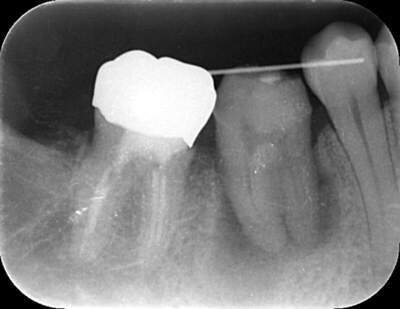

移植した歯のレントゲン写真

説明:

移植した歯の写真です。隣の歯とワイヤーで固定します。約3週間でワイヤーは外します。